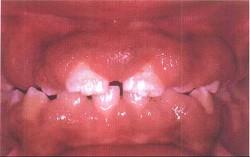

药物性牙龈增生的临床表现是 ( )

B上下前牙区较重,一般不易出血

C龈乳头可呈球状

D只发生于有牙区